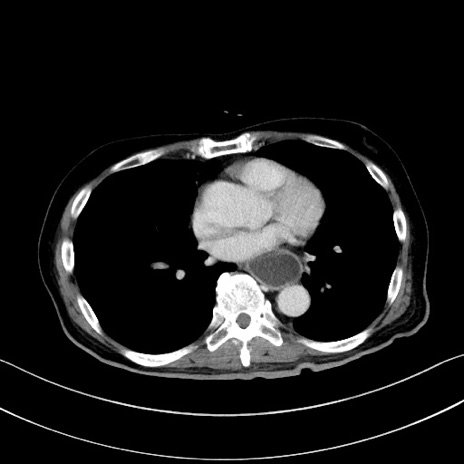

症例28(横断像)

【症例】60歳代男性

【主訴】嘔吐

【現病歴】胃癌にて胃全摘後。食思不振が悪化し、夜中に嘔吐することがある。

【既往歴】胃癌、胃全摘、脾摘、胆摘後

【データ】WBC 5900、CRP 10.56